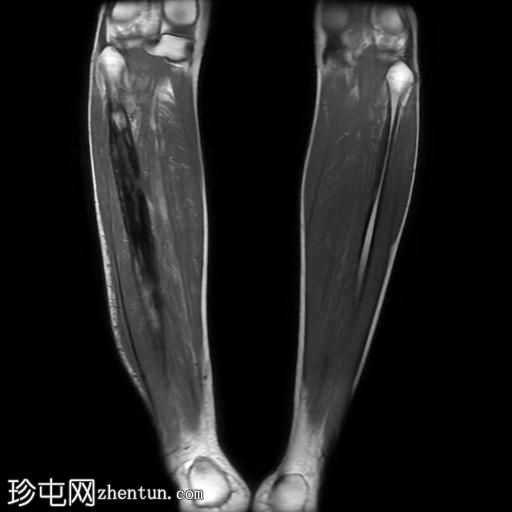

冠状位

T1加权像

腓骨可见广泛的骨髓水肿,伴有明显的皮质和骨膜增厚,整个腓骨均呈高信号。腓骨外侧中下三分之一交界处可见局灶性皮质破坏,并可见一条高信号瘘管延伸至周围皮肤。

腓骨弥漫性骨髓信号异常,伴有明显的皮质和骨膜增厚,窦道自腓骨延伸至皮下区域。MRI 影像学表现符合腓骨骨髓炎。